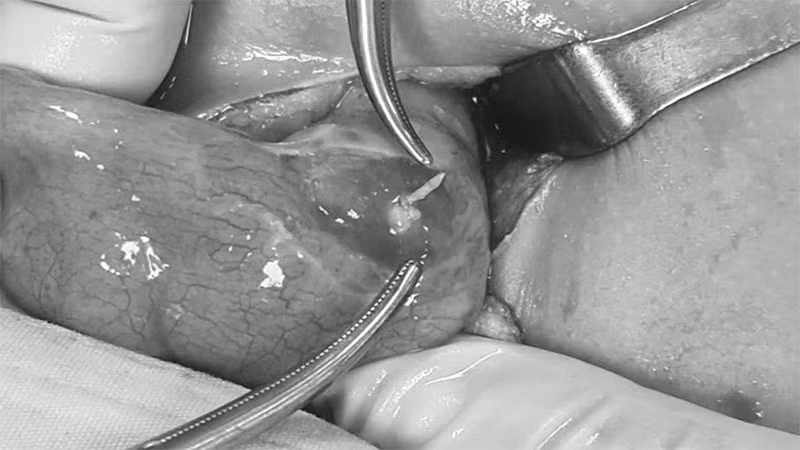

Trong quá trình phẫu thuật, các bác sĩ lấy ra một dị vật kích thước khoảng 4cm, nghi là xương cá xuyên thủng manh tràng. Sau khi được phẫu thuật thành công, sức khỏe cháu Q đã ổn định.

Khúc xương cá đâm thủng ruột cháu Q. (Ảnh: Bệnh viện cung cấp).